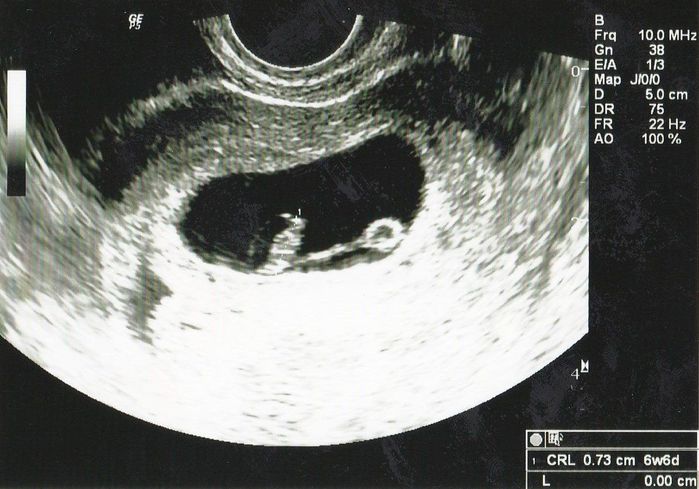

妊娠6週目のエコー写真 心臓の動きが確認できてひと安心

CRL=0.73cm

おなかの赤ちゃんは元気でいるのかどうか不安だった2週間を経て、やっと検診の日が来ました。黒い空間(子宮)が大きくなっていて、赤ちゃんのお部屋が大きくなってうれしかったのを覚えています。医師から「心拍が確認できたので、次回の検診までに母子手帳をもらってきてください」と言われ、次回(2週間後)までは時間はたくさんあるのに、うれしくて、その足で市役所の休日窓口へ母子手帳をもらいに行きました。妊娠初期は何があるかわからないと思っていたので、両親への報告は安定期に入ってからと考えていたのですが、喜びを誰かに伝えたくなり、実父母にはこの日に電話で報告してしまいました。